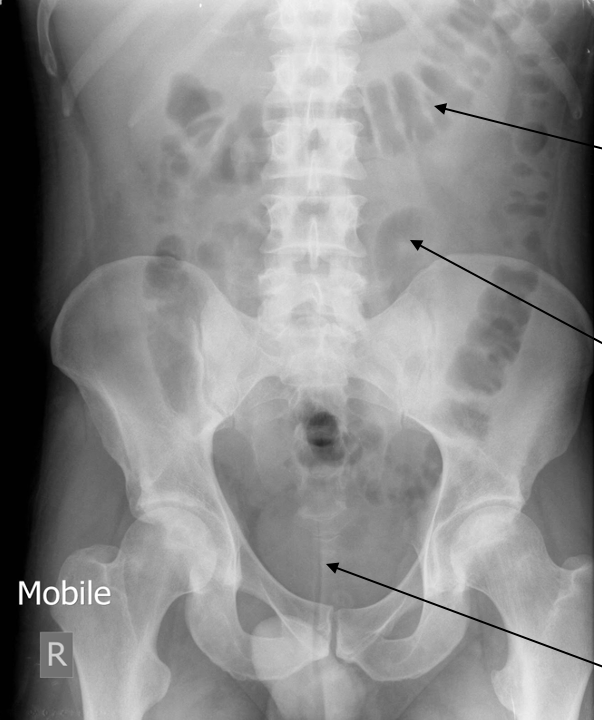

Label the structures

Top left → liver edge

Bottom left → kidney

Top right → spleen

Middle right → stomach

Bottom right → psoas

Top → large bowel

Middle → small bowel

Bottom → bladder